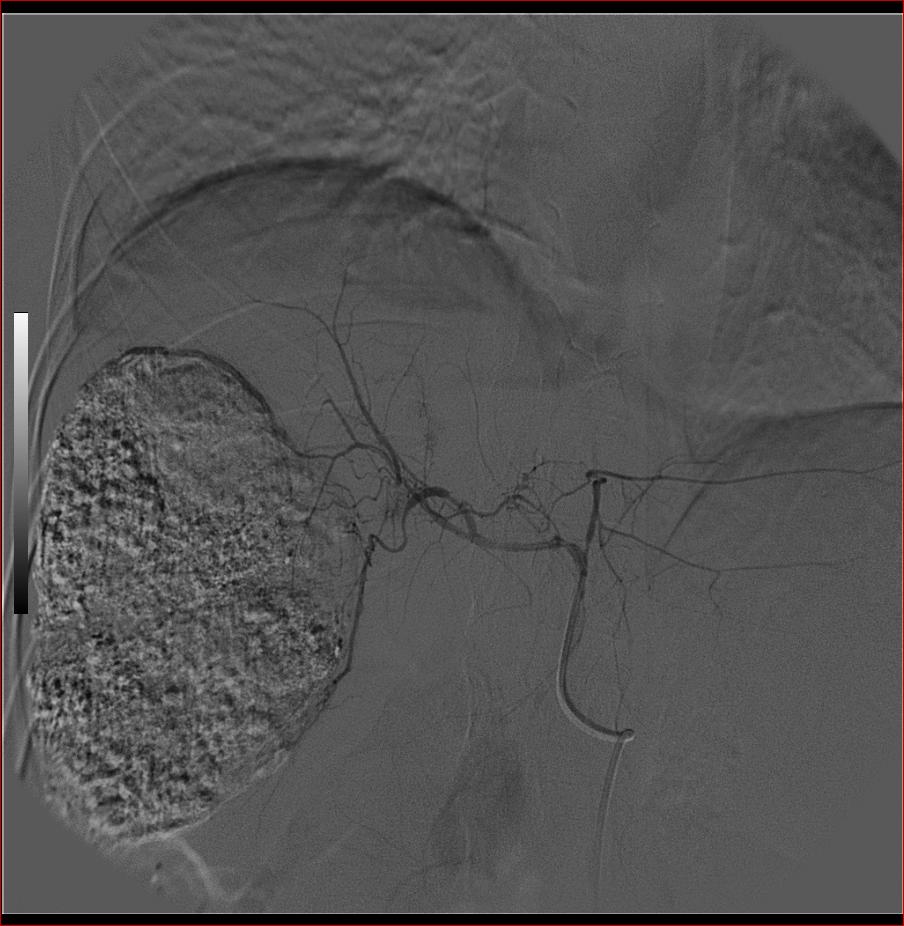

第二次(50天后)

栓塞的非常理想。

巨块型肝癌介入术后,肝左叶有转移吗(第二次进行肝左动脉栓塞了吗?)